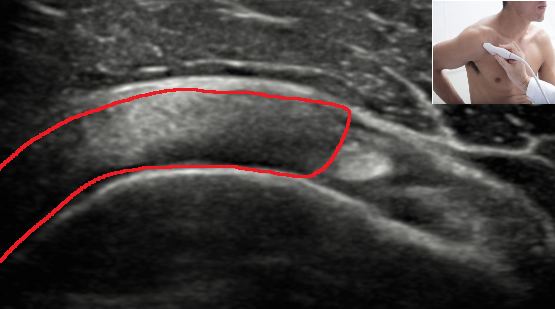

QUAL A ESTRUTURA ASSINALADA NA IMAGEM OBTIDA EM UMA ULTRASSONOGRAFIA DE OMBRO?

PORÇÃO EXTRA ARTICULAR DO TENDÃO DA CABEÇA LONGA DO BÍCEPS BRAQUIAL